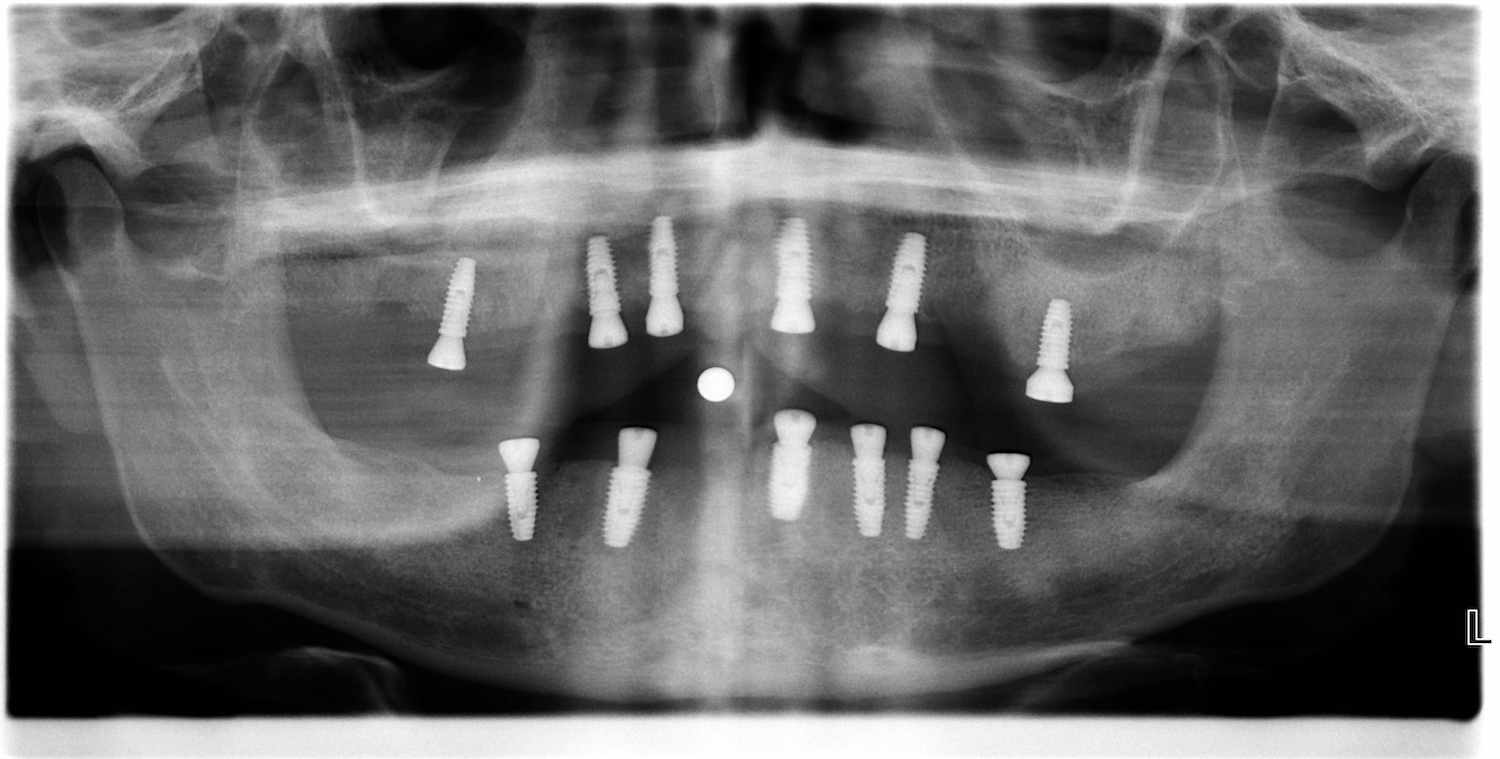

V posledních letech vidíme velký nárůst implantologických prací. Zhotovujeme náhrady na téměř 40 různých implantologických systémů, z nichž každý má několik variant podle typu, velikosti nebo řady implantátů. Každý implantát je jinak zavedený, a tak musíme vždy pečlivě rozhodnout, jaký cut použijeme podle toho jak hluboko je implantát zaveden.

Vnímáme také změnu preferencí lékařů – šroubované fixace jsou stále oblíbenější, ale někteří lékaři stále ještě dávají přednost cementovaným náhradám. Často také řešíme implantáty s odlišným sklonem, kde musíme rozhodnout, zda je nutné použít multiunit abutment.

Tohle všechno dělá práci s implantáty velmi komplexní. Není to jen o technice, ale hlavně o zkušenostech a schopnosti správně vyhodnotit každý případ.